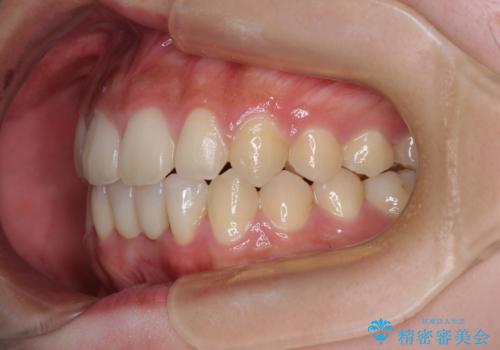

矯正治療終了後に速やかにオールセラミックブリッジを装着していくこととしました。

結婚式の予定があるとのことで、できる限り歯列を整え、挙式直前で残った乳歯を抜歯してブリッジの仮歯を装着するプランを立てたのですが、途中妊娠をされたため、麻酔をするタイミングを検討し、うまく前歯を整えることができました。